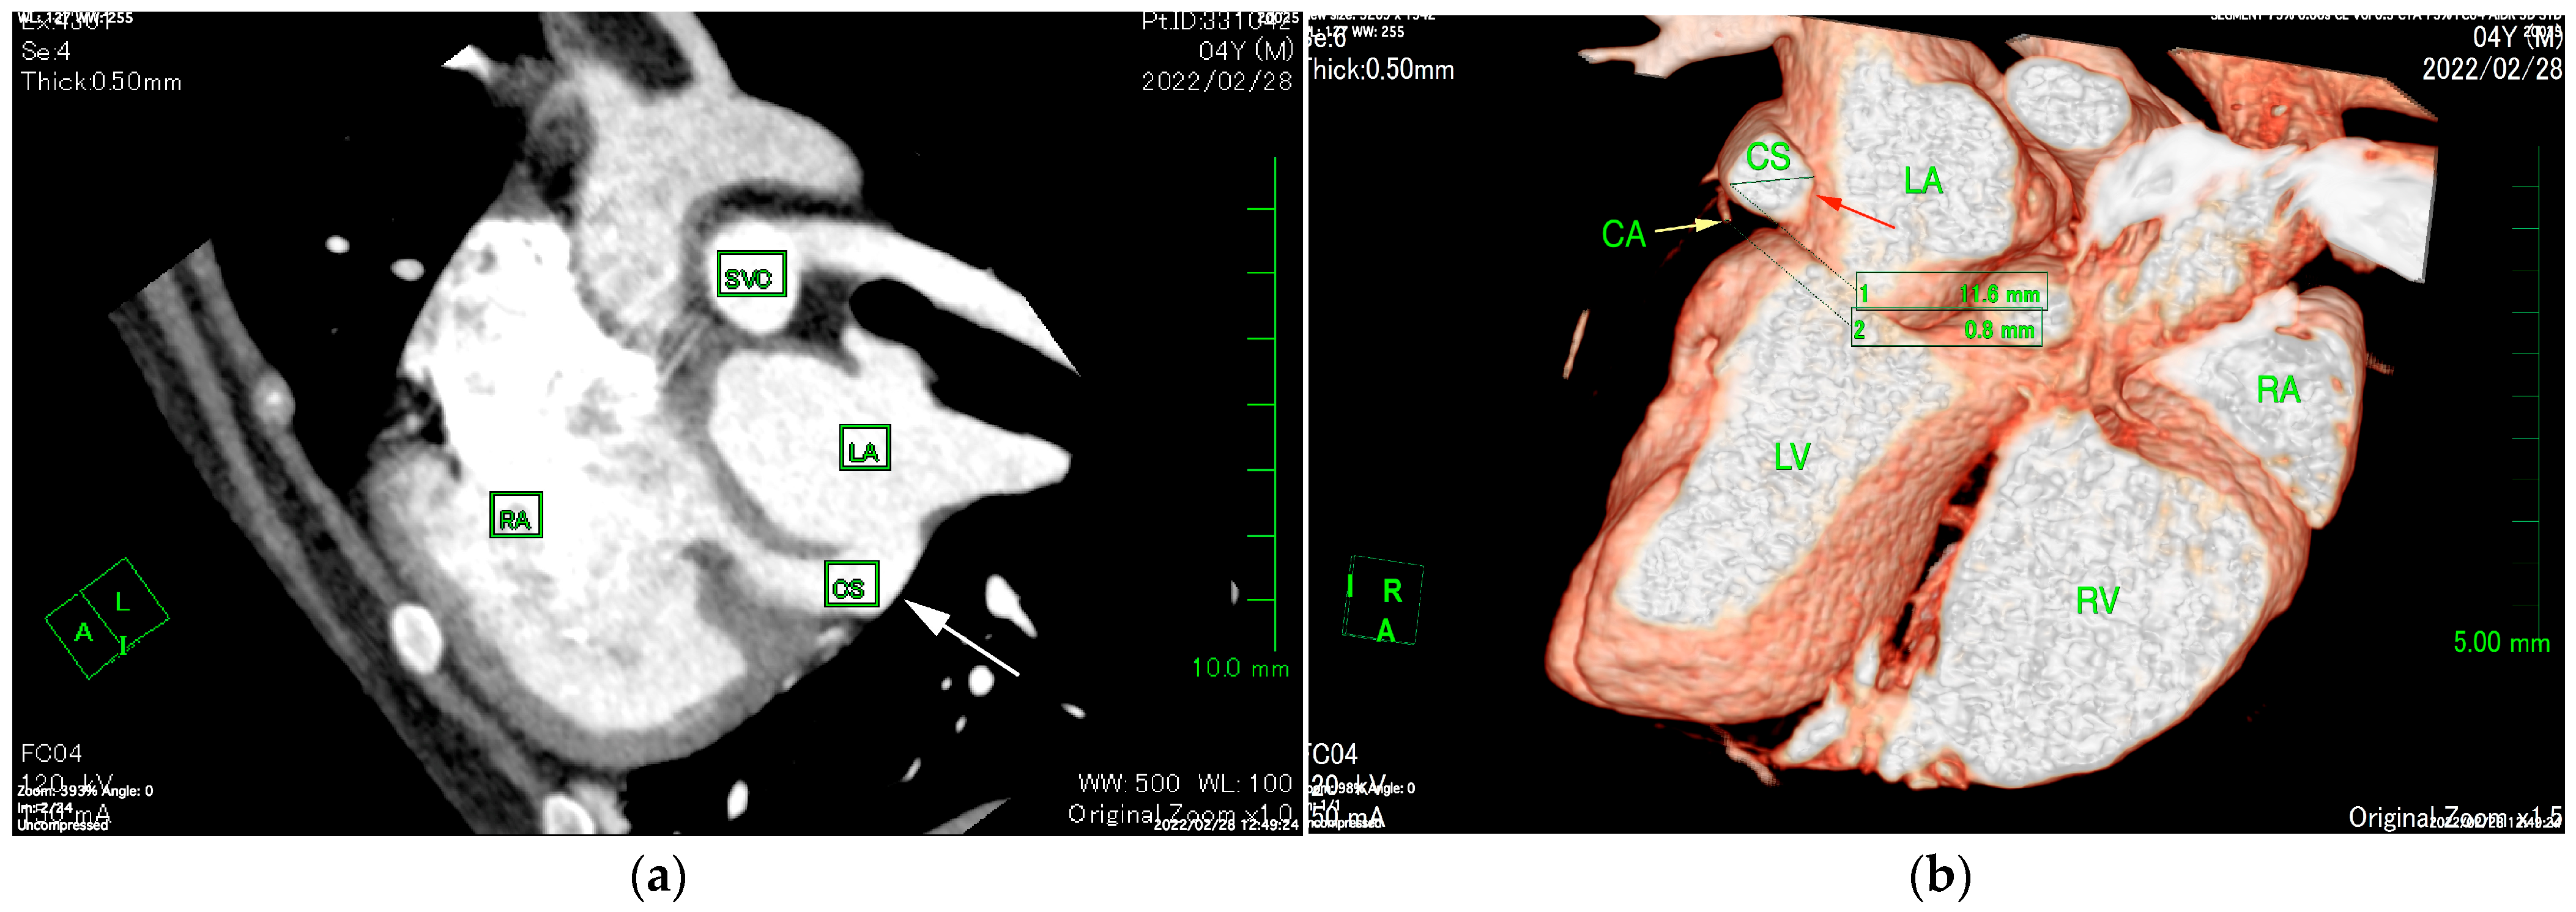

The TTE was performed using LISSENDO 880LE (Fujifilm Ltd., Tokyo, Japan) equipped with the 9–12 MHz phase array transducer probe (Fujifilm Ltd., Tokyo, Japan). TTE revealed trivial tricuspid regurgitation (TR), a pulmonary to systemic blood flow ratio (Qp/Qs) of 1.28, and there were no signs of a flattened ventricular septum. A left-to-right shunt, indicated by an irregular blood flow from the vicinity of the LA to the RA, was seen, although based on the evidence given at that time, it was possible that the blood flow was not actually within the heart. Conclusively, ASD was strongly suspected, although there was no opening found at the typical location during the TTE (Figure 1). Otherwise, the TTE evaluation revealed that other parameters were within normal limits. The results from the TTE were insufficient for a definitive diagnosis, so plans were made to further investigate with an ECG-gated CT.

Figure 1. Right parasternal long-axis four-chamber view of transthoracic echocardiography at the time of arrival. Transthoracic echocardiography shows an irregular communication between the left atrium and right atrium (arrow). From this image, it is unclear whether the blood flow is within the heart. RA, right atrium; RV, right ventricle; LA, left atrium; LV, left ventricle.